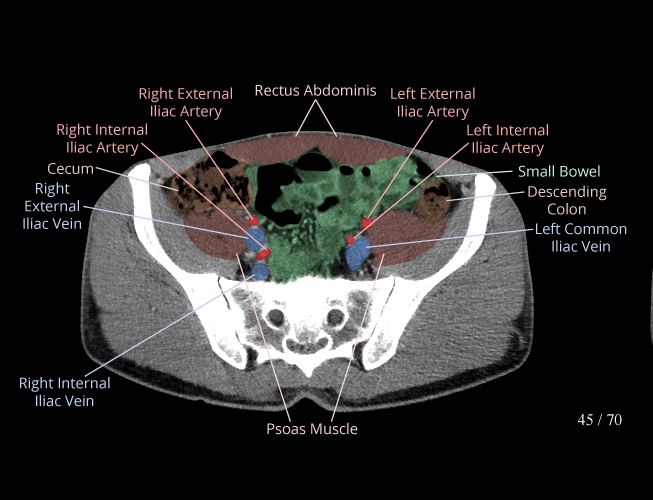

Body

Covers abdominal CT anatomy.